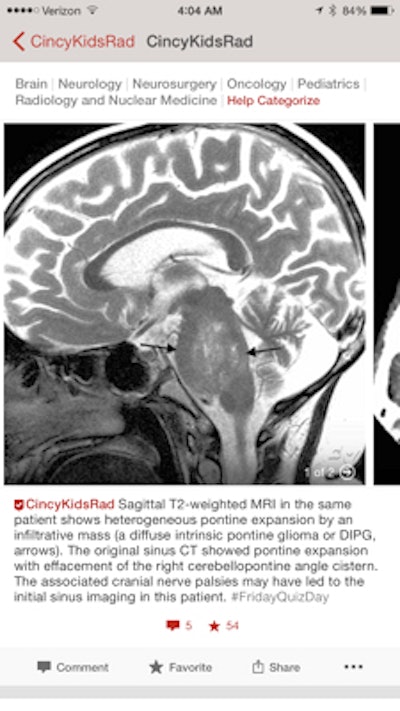

Next we moved to Instagram. We thought that Instagram was uniquely suited for radiology education because it focused on the image. We worked to create a curriculum where we shared a teaching case every day of the week. We set up a repeating series of hashtags to help our audience know what to expect each day (#MSKMonday, #TummyTuesday, #NeuroWednesday, #ThoraxThursday, and #FridayQuizDay). We found that Instagram was a great medium for teaching and that we could reach a large number of people with each post.

The content on Figure 1 and Instagram is similar. We post new cases five days a week, following the same schedule we devised for Instagram. The differences in content are related to differences between the two applications. The first difference is that Figure 1 allows us to upload more than one image per post. This is useful to show multiple findings or multiple views. Another cool feature of Figure 1 is the ability to upload an entire series. This is extremely helpful to allow users to scroll through a CT scan and understand the scope of the abnormality. Figure 1 also has more stringent limits on the amount of text allowed with each post (400 characters). This has forced us to make our teaching points more concise.